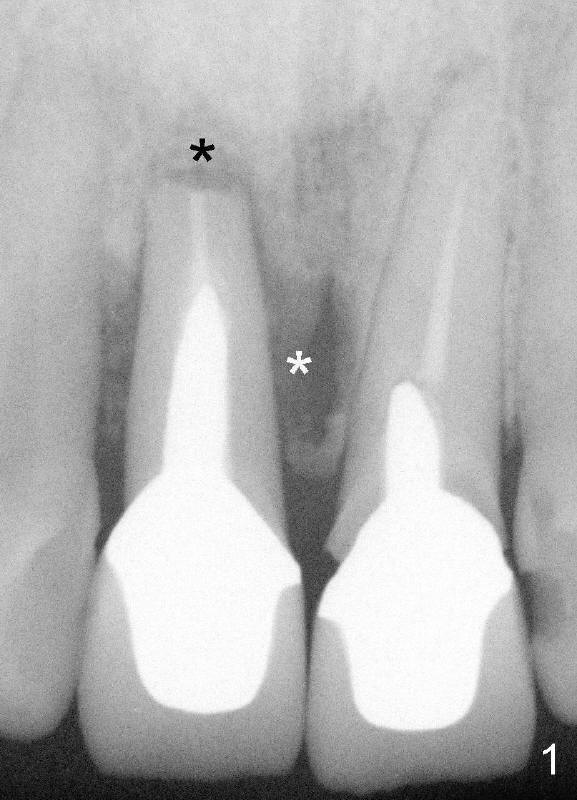

Fifty-five-year-old lady has had pain and swelling associated with #8 for a while in spite of apicoctomy in home country (Fig. 1 and 1' *, > (fistula)).  #9 is prosthodontic failure (Fig.1').  Both teeth are extracted at the same time.

Wounds heal uneventfully. Two months later, an implant is placed at the site of #8 (Fig.5).  Fig.4 is a preop X-ray, showing graft (*).  Two weeks later, swelling and pain recur (Fig.7).  Amoxicillin 500 mg tid is prescribed for a week.  Symptoms and signs improve after antibiotic treatment (Fig.8).  A month later, the patient complains tenderness on touching the implant of #8 without swelling.  A X-ray film is taken (Fig.6).  The symptom is again controlled while taking oral Clindamycin and relapses when treatment is terminated.  What should we do?